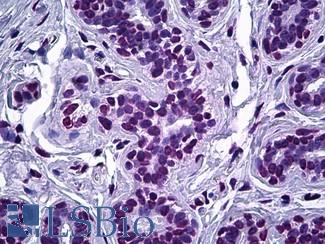

ACPP (PSAP)

Anti-Prostatic Acid Phosphatase antibody IHC of human prostate. Immunohistochemistry of formalin-fixed, paraffin-embedded tissue after heat-induced antigen retrieval. Antibody LS-B3108 concentration 5 ug/ml.

FOLH1 (PSMA)

Anti-FOLH1 / PSMA antibody IHC of human prostate. Immunohistochemistry of formalin-fixed, paraffin-embedded tissue after heat-induced antigen retrieval. Antibody LS-B2542 concentration 10 ug/ml.